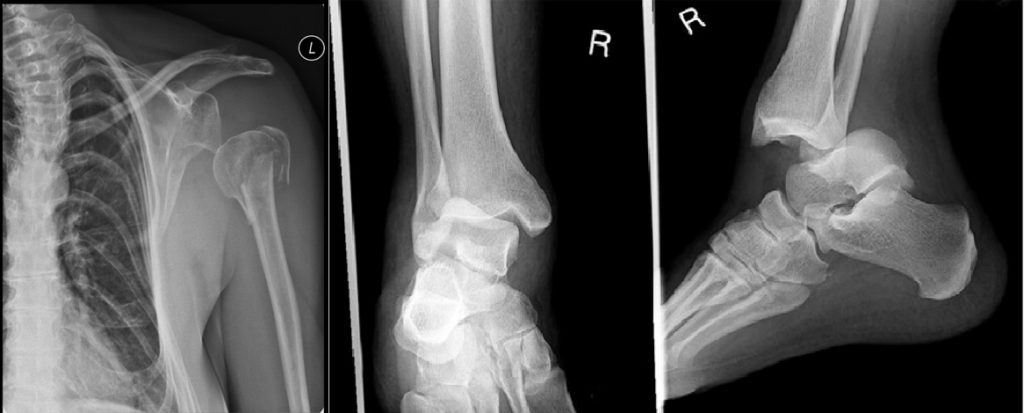

- Dislocation (Luxation)?

| Joint | Common Features |

|---|---|

| Shoulder | Most common; anterior dislocation often seen |

| Elbow/Wrist | Often with associated fractures |

| Fingers | IP joint involvement |

| Knee/Ankle | Often high-force injuries with fractures |

Direction of dislocation: anterior/posterior, superior/inferior